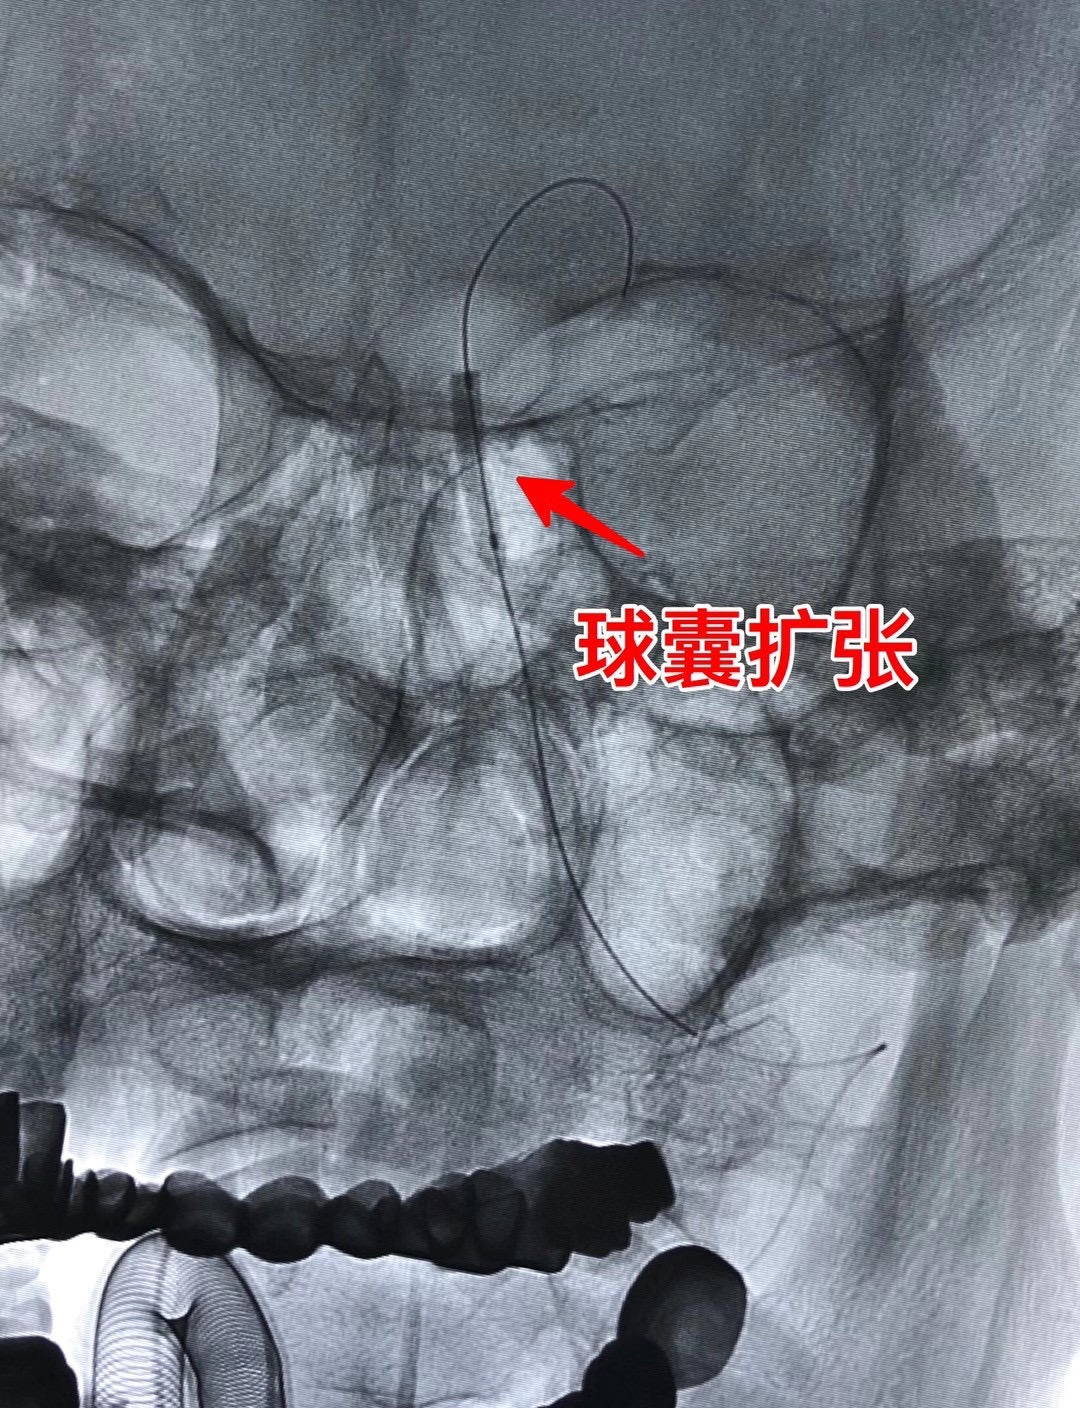

近日,21点玩法研究所 神经内科介入团队完成多例高难度、高风险的颅内动脉狭窄支架置入术及急诊动脉闭塞血管开通手术,成功挽救了多名危重缺血性卒中患者,再次彰显团队雄厚的技术实力及精益求精的专业态度。

张某,71岁,1年前因头晕就诊于当地21点游戏规则 ,行头颅MRI诊断小脑梗死,虽按照脑血管病二级预防给予药物对症治疗,但头昏症状持续存在,近期甚至出现发作性意识丧失,患者症状影响生活不说,更是让家人担心其生命安全,为进一步诊治,慕名就诊于神经内科王新来主任脑血管病专科门诊,王主任细致地询问了患者病史,认真地审阅了头颅影像资料后,发现了患者发病的元凶——基底动脉狭窄,随即将患者收住入院,入院后及时、全面完善相关检查,提示患者基底动脉供血区脑灌注严重不足,于是神经内科团队进行了术前讨论,明确了手术的可行性和必要性,王新来主任医师、雷辉主任医师带领介入小组团队,制定了周密的手术方案,并与患者及家属做了充分的术前沟通,于2020818日在介入室为患者实施手术,术后患者脑灌注明显改善,头昏症状显著缓解,已于近日顺利出院。

(患者全脑血管造影提示基底动脉狭窄75%  底动脉狭窄的Tips

雷辉主任医师介绍:基底动脉是脑内重要血管,由左、右两支椎动脉汇合而成,常称为椎基底动脉系统。这个系统在颅腔内的分支为脊髓、脑干、小脑和间脑后部供血。基底动脉狭窄导致后循环缺血,临床上往往会表现为如头痛、头晕、黑曚等症状,重者还可能出现四肢瘫痪、意识障碍,甚至死亡。重度基底动脉狭窄的患者,达到手术指征时理论上应尽早行支架植入成形治疗解除狭窄,预防危及生命的卒中复发。但基底动脉因其特殊的解剖结构,支架置入,面临着分支多、斑块移位可能会引起雪犁效应导致穿支动脉闭塞加重病情,斑块脱落至远端甚至会造成严重的致死性并发症即基底动脉尖综合征,也有可能会出现局部的脑血流过度灌注出血等等各种风险,因此属于血管介入领域的超高难度手术,该技术也标志着神经介入领域的最高技术水平。